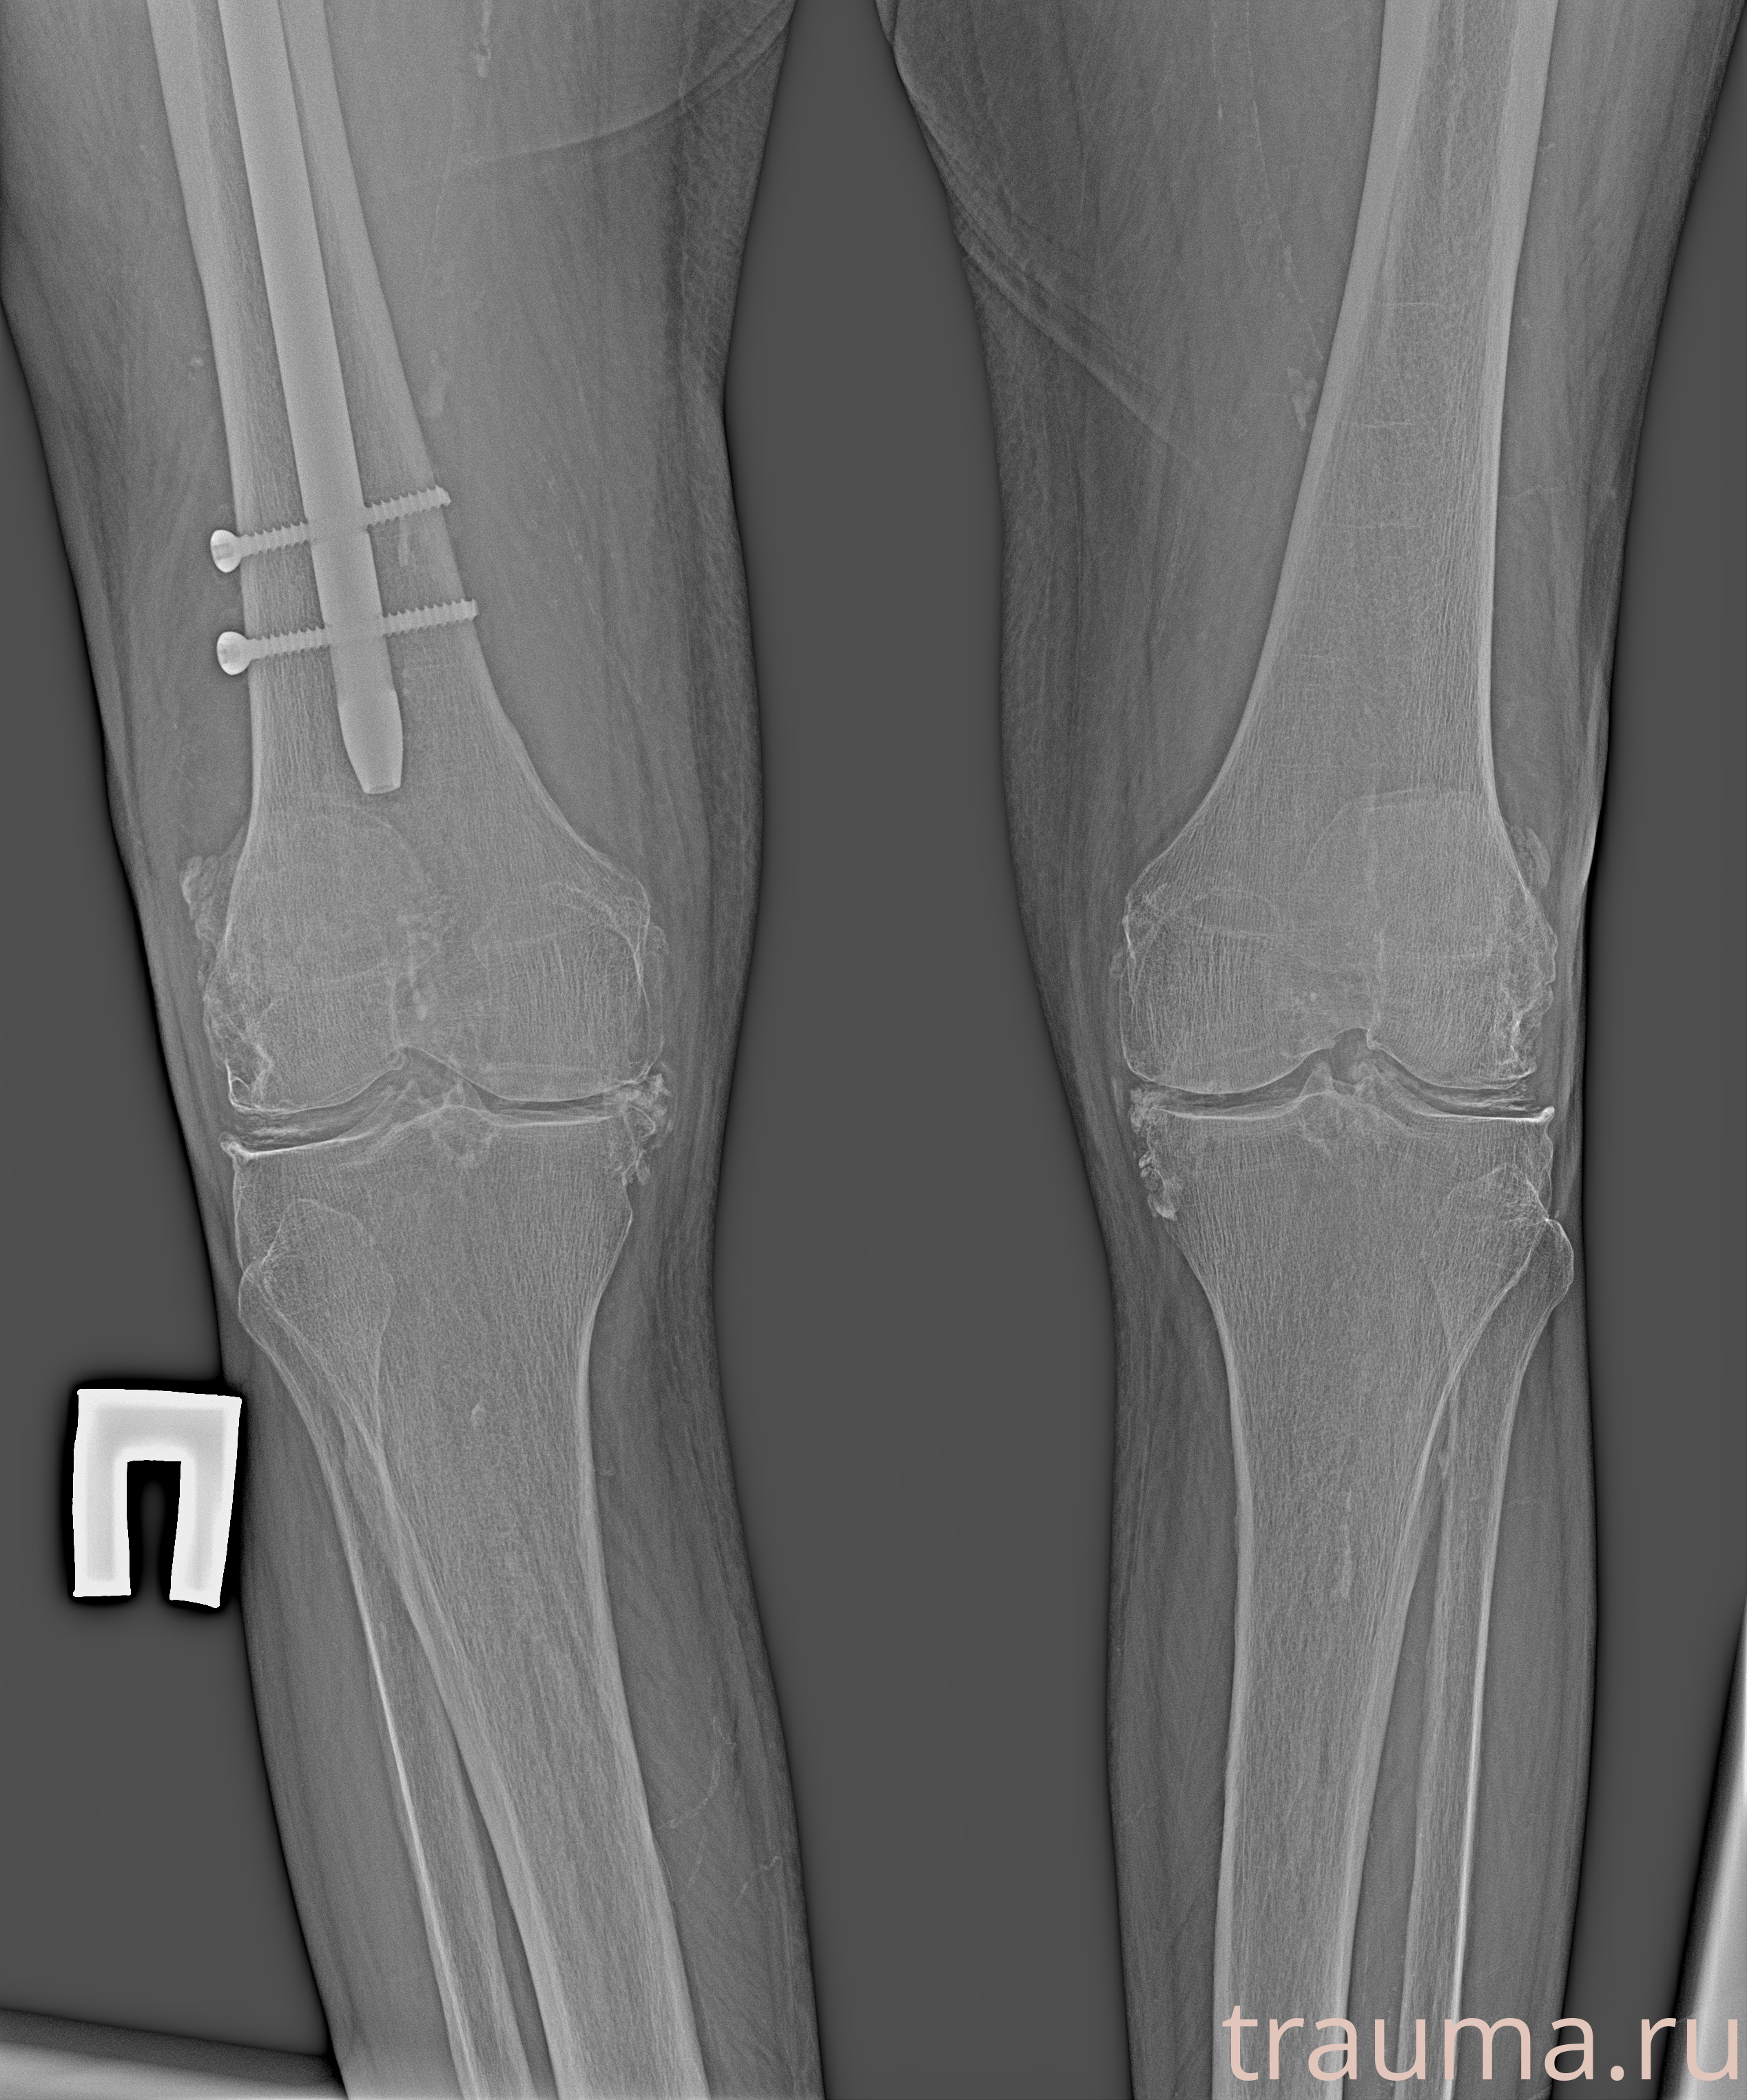

Рентгенограммы

Рентген на дому: по вашему адресу приезжает врач-рентгенолог, травматолог-ортопед с мобильным рентгеновским аппаратом, проводит диагностику травмы или заболевания, делает необходимые рентгенограммы, дает рекомендации по дальнейшему лечению. Получить качественные снимки в домашних условиях возможно благодаря уникальной методике, разработанной МосРентген Центром для института  Склифосовского